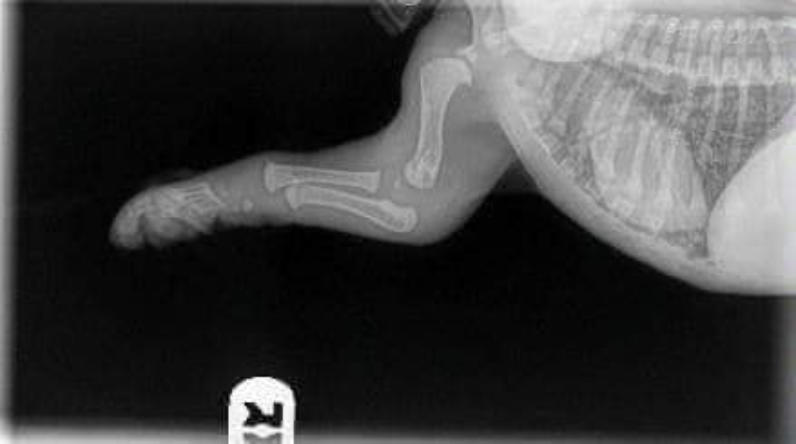

Was prägt Welpen fürs Leben? Was bedeutet Prägung überhaupt? Wenn Sie das Wort „Prägung“ mal im Internet eingeben werden Sie feststellen, dass es verschiedenste Definitionen gibt. Im Zusammenhang mit der Hundehaltung spricht man eher von „prägeähnlichen Lernprozessen“. Dies liegt daran, dass im wissenschaftlichen Sinne Prägung ein unumstößlicher Lernvorgang ist. Hunde jedoch können ihr Verhalten verändern und daher ist einmal Erlerntes keineswegs irreversibel. Um es nicht unnötig kompliziert zu machen, lassen wir die Wissenschaft außen vor und nennen den Begriff nachfolgend dennoch Prägung. Die Neonatale- und Übergangsphase Jeder Züchter und jeder Welpenbesitzer legt größten Wert darauf, seinen Welpen bestens aufs Leben vorzubereiten. Von Geburt an ist es für den Welpen wichtig, dass er durch sein genetisch fixiertes Verhalten positive und negative Erfahrungen macht. Welpen können trotz verschlossener Ohrkanäle Schreckreaktionen auf laute Geräusche zeigen, warm und kalt unterscheiden und auch Schmerzreaktionen zeigen. Milder Stress ist hier das Zauberwort. Dieser fördert das Immunsystem und befähigt den Organismus mit Stress und Belastung umzugehen. Zum Ende der 3. Lebenswoche bekommen Umweltreize eine Bedeutung für den Welpen. Seine Motorik wird kontrollierter und die Schlafperioden werden kürzer. Die Sozialisationsphase beginnt In dieser Phase finden wichtige Wachstums- und Differenzierungsprozesse im Gehirn statt und sorgen so dafür, dass sich die Neuronen im Gehirn untereinander vernetzen und der Welpe somit besser lernen kann. Ganz besonders wichtig ist es in dieser Phase, ihn weder in Watte zu packen noch zu überfordern. Bieten Sie ihm die Möglichkeit Kinder, ältere Menschen und Erwachsene kennen zu lernen oder auch Erfahrungen im Garten zu sammeln. Besonders sollten Sie in dieser Phase darauf achten, dass der Welpe sich selbstständig in verschiedenen Situationen bewegen und darf. Der Welpe soll eigenständig lernen… Demutsgesten zu zeigen, mit Angst fertig zu werden, seine Zähne dosiert einzusetzen, Aggressionen und Frustrationen abzubauen, und nach Lösungen zu suchen. Der Welpe muss lernen, sein Verhalten der Situation anzupassen Nicht alles im Leben läuft so, wie er es wünscht und deswegen geht die Welt nicht unter. Diese Lernvorgänge sind für ihn äußerst wichtig, um im späteren Leben seine Reaktionen dem Kontext anpassen zu können. Der kleine Kampf mit seinen Geschwistern an der Futterschüssel, ist für diesen Lernprozess zum Beispiel sehr zuträglich. Ein ständig reichhaltiges Futterangebot würde den Lernprozess unterbrechen. Züchter und Welpenbesitzer müssen die Prägung fortsetzen Studien belegen, dass Welpen die sowohl beim Züchter als auch beim künftigen Welpenbesitzer betont ruhig aufwachsen, später die gelasseneren Hunde sind. Viele bekommen plötzlich wahnsinnigen Stress Auf einmal denken Sie an die Sozialisationsphase und meinen, sie müssten noch so viel erledigen. Der Welpe soll Busfahren, die Stadt kennenlernen, jegliche Menschen und Tiere in der Nachbarschaft erleben und und und… All dies kann einen Welpen ganz schön überfordern Wir sollten unsere Ansprüche wirklich umsichtig dem einzelnen Welpen und der zukünftigen Lebenssituation anpassen. Wer bekommt den Welpen? Welche Ansprüche haben Sie? Möchten Sie einen ruhigen oder agilen Hund? Dementsprechend sollte auch seine Förderung angepasst sein. Wenn Züchter sich zu starke Mühe geben und dem Welpen alle Umweltsituationen aussetzen wollen, wird ihn später wenig beeindrucken. Der Mittelweg ist auch hier wieder ideal. Nehmen Sie sich Zeit Bei all dem Freizeitstress, dem Welpen häufig ausgesetzt sind, wird eines gerne vergessen: Welpe und Familie müssen sich kennen lernen, um eine Bindung zueinander aufbauen zu können. Dazu sind die alltäglichen Situationen in der Regel für alle Beteiligten schon Herausforderung genug. Welpengruppen, Café und was es sonst noch so gibt, sollte da zunächst nebensächlich sein. Nur Sie und Ihr Welpe zählen und seien Sie gewiss: Ihr Welpe wird auch später noch lernen können Bus zu fahren. Sorgen Sie zunächst für eine gute Mensch-Hund –Beziehung. Wenn das stimmt, dann kann die Erziehung anfangen. Das A und O der Bindung Hundehalter verstehen unter Bindung Unterschiedliches. Während die Einen Bindung mit Erziehung verwechseln, verstehen die Anderen darunter, dass der Hund die Nähe seines Menschen sucht. Doch Bindung ist viel mehr als das. Bindung ist ein unsichtbares Band Egal ob in der Tierwelt oder bei uns Menschen: Schon die Kleinsten lernen, sich zu binden, wobei man Bindung keinesfalls mit Abhängigkeit verwechseln darf. Die kindliche Abhängigkeit nimmt im Laufe des Lebens ab, wobei die Bindung ein Leben lang bestehen kann. Warum binden sich Lebewesen? In der Tierwelt dient Bindung schlichtweg dem Überleben. Gemeinsam ist man stark und daher kommen als Bindungspartner ausschließlich Jene in Frage, die man gut kennt und auf die man sich verlassen kann. Genau wie wir Menschen, suchen auch Hunde nach Sicherheit und Geborgenheit. Wissenschaftler haben heraus gefunden, dass diese ähnlichen Bedürfnisse, die vertrauensvolle und tiefe Bindung zwischen Mensch und Hund erklären. Hat Bindung etwas mit Nahrung zu tun? Absolut nicht. Zwar schätzen unsere geliebten Vierbeiner Hundekekse sehr, jedoch sind sie nicht verantwortlich für eine tiefe Bindung. Vielmehr ist die Sicherheit, Geborgenheit und Akzeptanz wichtig für eine gute Bindung. Das erklärt auch, warum sowohl Hund als auch Kind in einer Gefahrensituation sofort zur Mutter oder zum Hundebesitzer laufen. Wie erreichen Sie eine gute Bindung zu Ihrem Hund? Fühlt ihr Hund sich unsicher oder hat er sogar Angst, wird er versuchen durch fiepen, bellen, heulen, lecken, anstubsen, Körper- oder Blickkontakt Nähe zu Ihnen herzustellen. Reagieren Sie auf diese Zeichen angemessen und selbstsicher. Sofort wird ihr Hund sich sehr viel besser fühlen. Verletzt sich Ihr Tier, reagieren Sie sofort, um ihm zu helfen. Beantworten Sie seine Zeichen, wie zum Beispiel Blickkontakt, stets mit einem freundlichen Wort. Zeigen Sie Ihrem Hund, dass Sie ihn wahrnehmen und schätzen. Seien Sie feinfühlig und dies immer, dann können Sie ein unsichtbares Band aufbauen, welches ein Leben lang erhalten bleibt. Welche Fehler kann man machen? Verwechseln Sie Bindung nicht mit Erziehung! In der Erziehung ist es die wohlgemeinte Konsequenz, die ans Ziel führt. Bei der Bindung ist es das Gefühl und Ihre Feinfühligkeit, was Sie verbindet. Reagieren Sie stets angemessen auf das Verhalten Ihres Hundes. Droht Gefahr schreiten Sie ein, aber lassen Sie sich zum Beispiel im Restaurant nicht von bettelnden Gesten beeindrucken. Dies betrifft nicht die Bindung, sondern ganz klar die Erziehung. Würden Sie in der Situation auf Ihren Hund eingehen oder gar ihm nachgeben, dann hat er sicherlich eines gelernt: Dass sein Verhalten erfolgreich war. Aber die Bindung bleibt davon unberührt. Fazit: Jeder schätze sich glücklich, den eine tiefe Bindung zu seinem Hund verbindet. Arbeiten Sie ein Leben lang daran. Dies lohnt sich, denn Sie werden reichlich dafür beschenkt. Wieviel Bewegung braucht ein Welpe ?? Golden Retriever Welpen befinden sich in den ersten 18. Monaten in einem Stadium der Knochenentwicklung. In dieser Zeit sind die Knochen sehr empfindlich, da sie noch weich sind dadurch nur wenig belastet werden sollten. Es gibt einige Punkte, die man unbedingt einhalten sollte: Absolutes Treppen-Verbot, tragen sie ihren Welpen also so lange es geht die Treppen auf und ab. Der Welpe muß unbedingt Ruhepausen mache, fordern sie ihn niemals zum Spielen auf, wenn er gerade schläft Vermeiden sie extreme Bewegungen, dazu gehören Spurts mit schnellen Stop Niemals an den Beinen oder der Rute ziehen Lassen sie den Welpen über keine Hindernisse springen - kein Agility bevor er 18. Monate alt ist. Beiss-Reiss Spiele vermeiden, sie können zur Gebißverformung führen Keine Fahrradtouren bevor der Hund ausgewachsen ist. Lassen sie ihn lieber auf einem Feld oder Wiese toben, der weiche Boden tut den Gelenken gut, auch Traben ist besser als Galoppsprünge. 5-Minuten Regel ein Welpe soll täglich nur 5 Minuten je Lebensmonat Bewegung haben. Körperliche Überanstrengung in Kombination mit hochkalorienhaltiger Fütterung führt neben dem genetischem Aspekt oft zu Gelenkerkrankungen wie HD/ED. Bewegen Sie im ersten Lebensjahr ihren Welpen lieber zu wenig als zu viel. Passen Sie das Tempo der Gassirunde an - ein strammer 20-minütiger Weg kann schon zu viel sein !